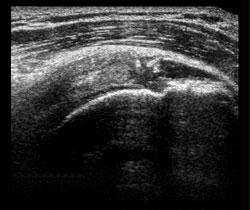

Ultrasound images can be useful in diagnosing tendon and ligament swelling, sprains or tears. Examples include rotator cuff injuries in the shoulder, Achilles tendon tears in the ankle and ligamentous strains in the knee. Abnormalities of the muscles can also be seen, such as tears and soft-tissue masses. Bleeding or other fluid collections within the muscles, ligaments, bursae and joints can also be detected.

The ultrasound image is immediately visible on a nearby screen that looks much like a computer or television monitor. The images can be captured for storage or printed. Most ultrasound studies are relatively quick and well tolerated by the patient. If scanning is performed over an area of tenderness, there may be minor pain associated with the procedure. Otherwise the procedure is painless.